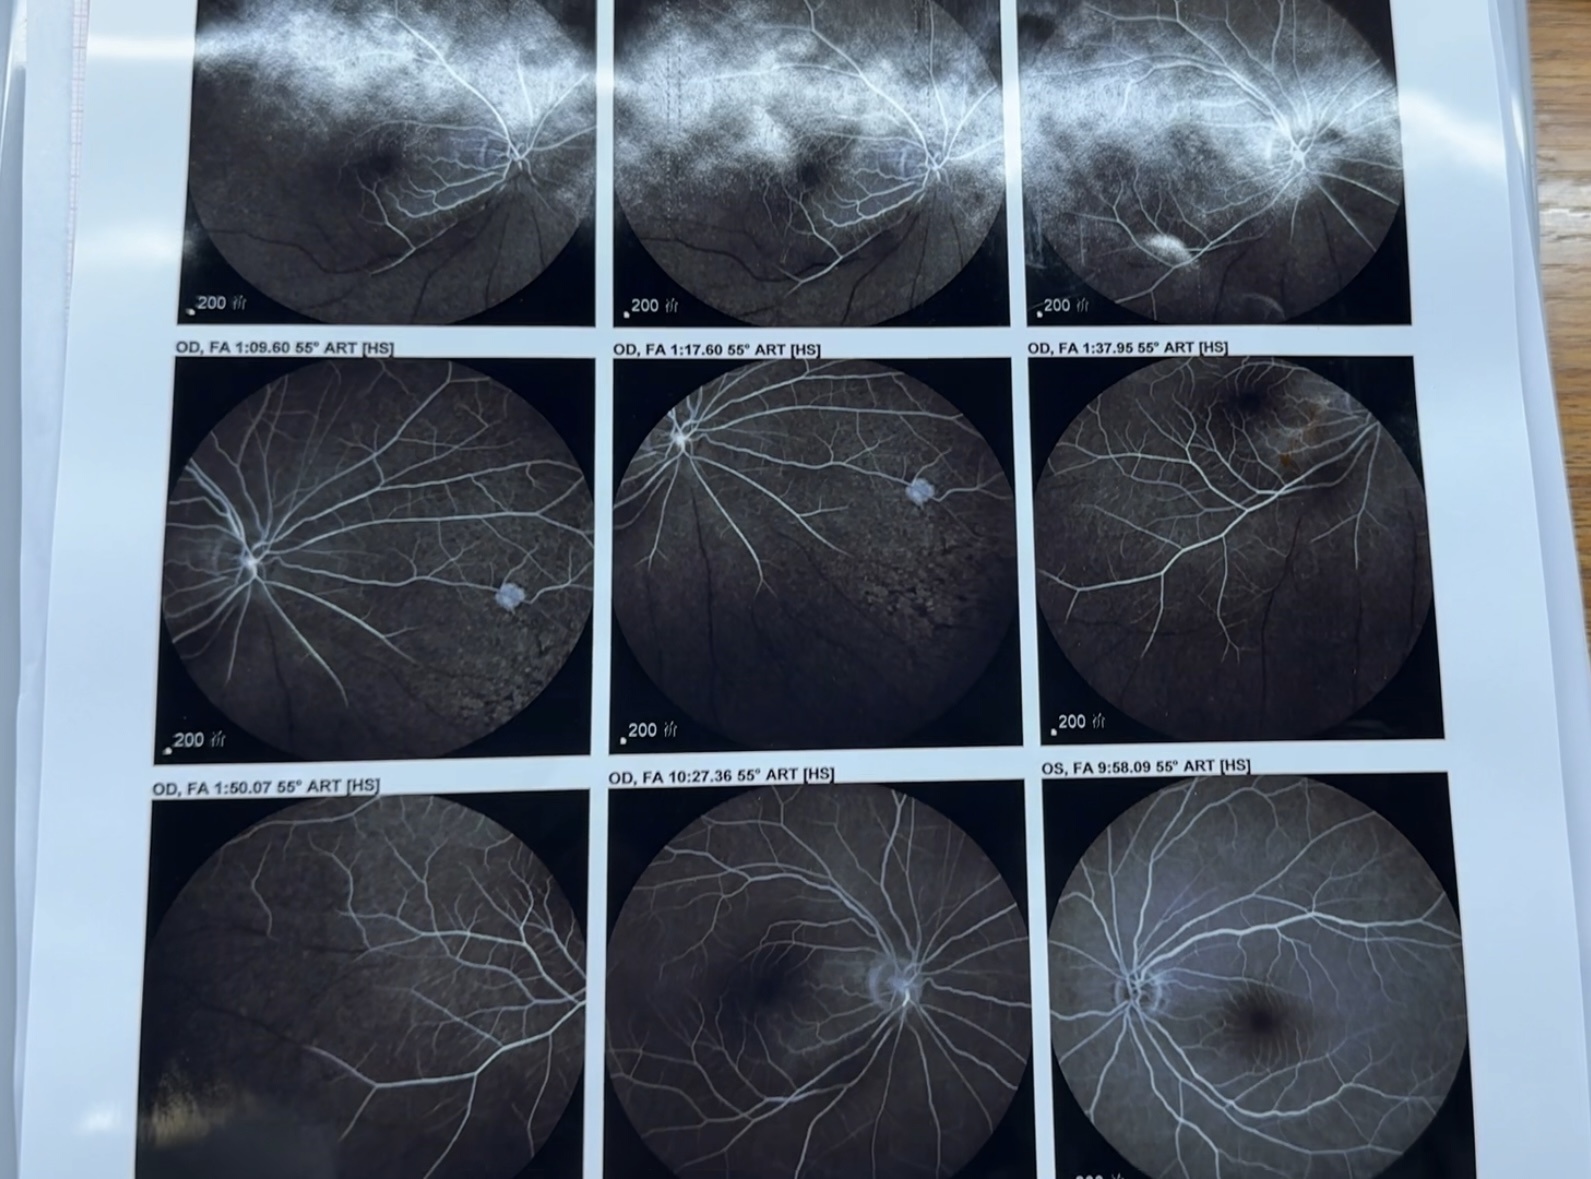

到医院后袁奶奶左眼的视力下降到只能近距离看清手指晃动的程度,经检查诊断为视网膜中央动脉阻塞,眼底病科接诊的沈易权医生立刻对她进行救治,但由于从发病到就诊期间耽误了4个多小时,错过最佳的黄金治疗时间,已造成不可逆的视力损伤,左眼很难恢复到患病之前的视力了。

沈易权介绍,视网膜中央动脉阻塞就是眼睛“中风”,和心梗、脑梗是一样的,都有黄金抢救期。近期医院共接诊了三例这样的患者,他们都是高血压人群,且没有进行常规的降压治疗。由于最近天气由冷转暖,血管扩张、栓子脱落,在基础病和季节变化双重加持下,导致视网膜动脉发生阻塞,而急性缺血,无痛性急剧视力下降甚至无光感。